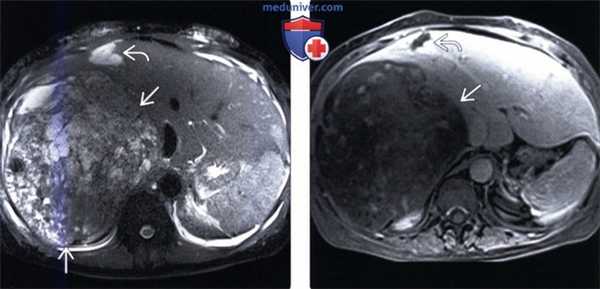

(Слева) На аксиальной Т2 ВИ МР томограмме у женщины 5 7 лет визуализируется большое объемное образование в печени, практически полностью замещающее правую долю. Сигнал в образовании неравномерно гиперинтенсивный, хотя и не настолько, как в другой опухоли (подтвержденной кавернозной гемангиоме).

(Справа) На аксиальной Т1 ВИ МР томограмме с контрастным усилением у этой же пациентки в периферических отделах гемангиомы визуализируются узлы, накапливающие контраст, в то время как в большей части саркомы не происходит накопления контраста. Опухоль была верифицирована как недифференцированная саркома с некротическими изменениями большей части опухоли и кровоизлияниями, что и предполагалось на МРТ.

3. МРТ признаки недифференцированной саркомы печени:

• Объемное образование большого размера, округлой формы, с наличием капсулы

• Центральный некроз, кровоизлияния, кистозные изменения:

о Характеризуются неоднородно гиперинтенсивным сигналом на Т1 и Т2 ВИ